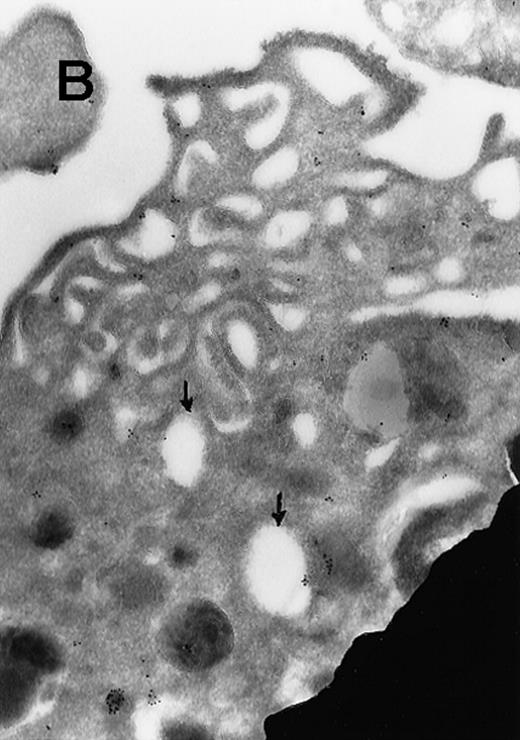

(A) Ultrathin frozen sections of rat platelets immunolabeled with antibodies to ERK (magnification ×45 000). (B) Well-developed demarcation membranes in a rat (Wistar), TPO-treated megakaryocyte7 9 immunostained with an antibody to Mst1 (magnification ×48 000), or (C) with an antibody to ERK, which recognizes ERK1 and ERK2 (magnification ×65 400). The arrows point to the demarcation membranes. The Mst1 antiserum (gift of Dr Jonathan Chernoff, Fox Chase Cancer Center, Philadelphia, PA) and anti-ERK2 (K-23) (Santa Cruz Biotechnology, Santa Cruz, CA) or TR2, anti-ERK (gift of Michael Weber, University of Virginia Medical School) were diluted 1:10.

In view of these reports, we determined the cellular localization of MAP kinase in megakaryocytes, with a particular attention to the platelet-yielding demarcation membranes.7As a control, we determined the localization of another TPO-upregulated serine/threonine kinase, Mst1.8 Our current Electron Microscopic (EM) studies, performed as we described before,9 reveal that a significant fraction of MAP kinase, but none of Mst1, localizes to the demarcation membranes. In resting platelets, MAP kinase is found in a cluster pattern associated with the plasma membrane (which is believed to originate from the megakaryocytic demarcation membranes),7 as well as over electron-dense cytoplasmic domains (Figure). In view of our finding that MAP kinase is localized to the demarcation membranes in megakaryocytes, it is of interest to note that this kinase was also shown to be localized in Golgi membranes and involved in their fragmentation during mitosis in a microtubule-dependent manner.10 Platelet fragmentation likely involves the cytoskeleton, and perhaps MAP kinases are also involved in this process.